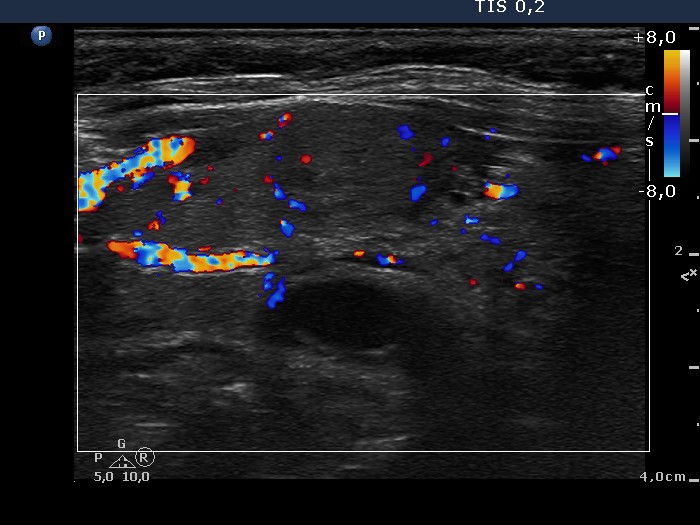

Ultrasonography. The thyroid was composed of multiple nodules with different echogenicities. There was a small hypoechogenic lesion above the right lobe.